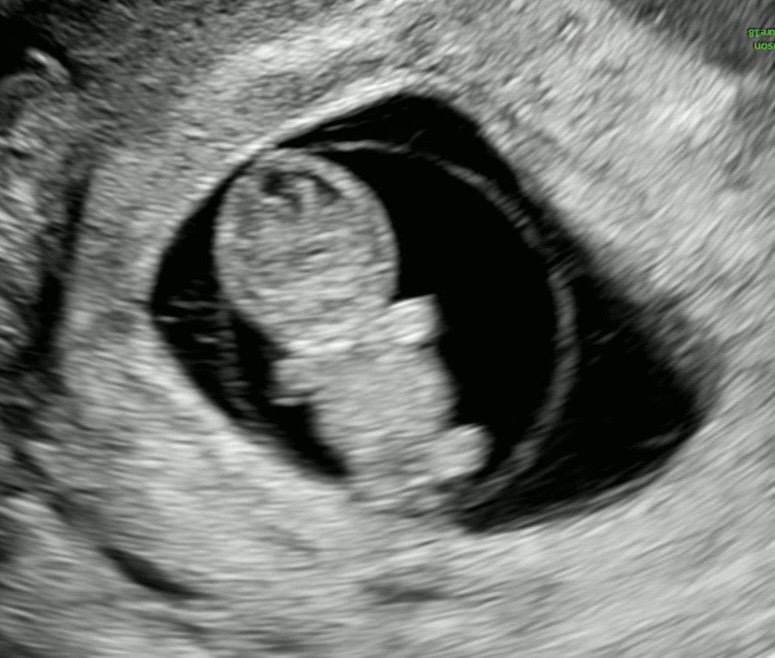

젤리곰이 된 아기

꼬물꼬물 움직이기도 하고 사람 형태를 갖춰가는 모습이 너무 너무 귀엽다 🩵

9주 0일이에요🐣

오늘 찍고 왔어요~ 9주 0일이에요!